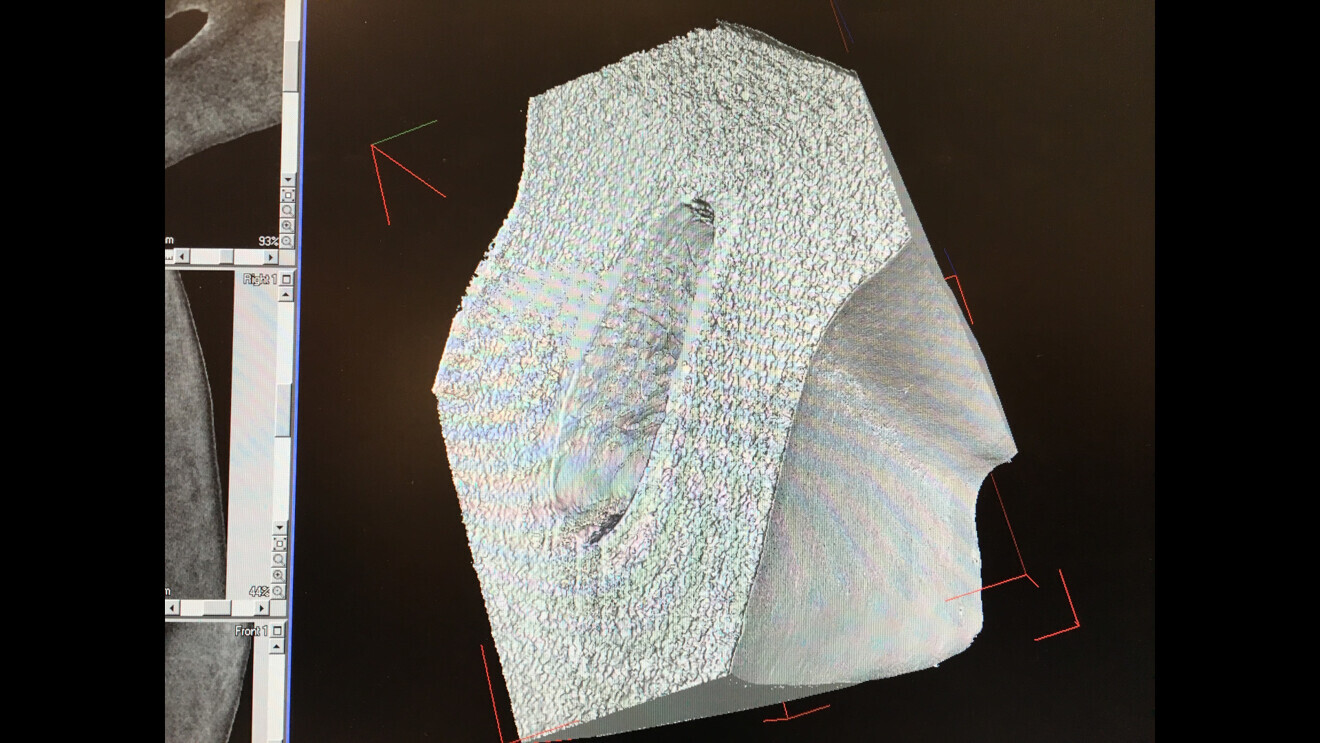

Examples of 3D scans provided by Dr Kustra of his own face. Taken with a Siemens Somatom Sensation Cardiac 64 spiral CT scanner, such images are useful for virtual endoscopy planning.

A digital model being prepared for a virtual endoscopy.